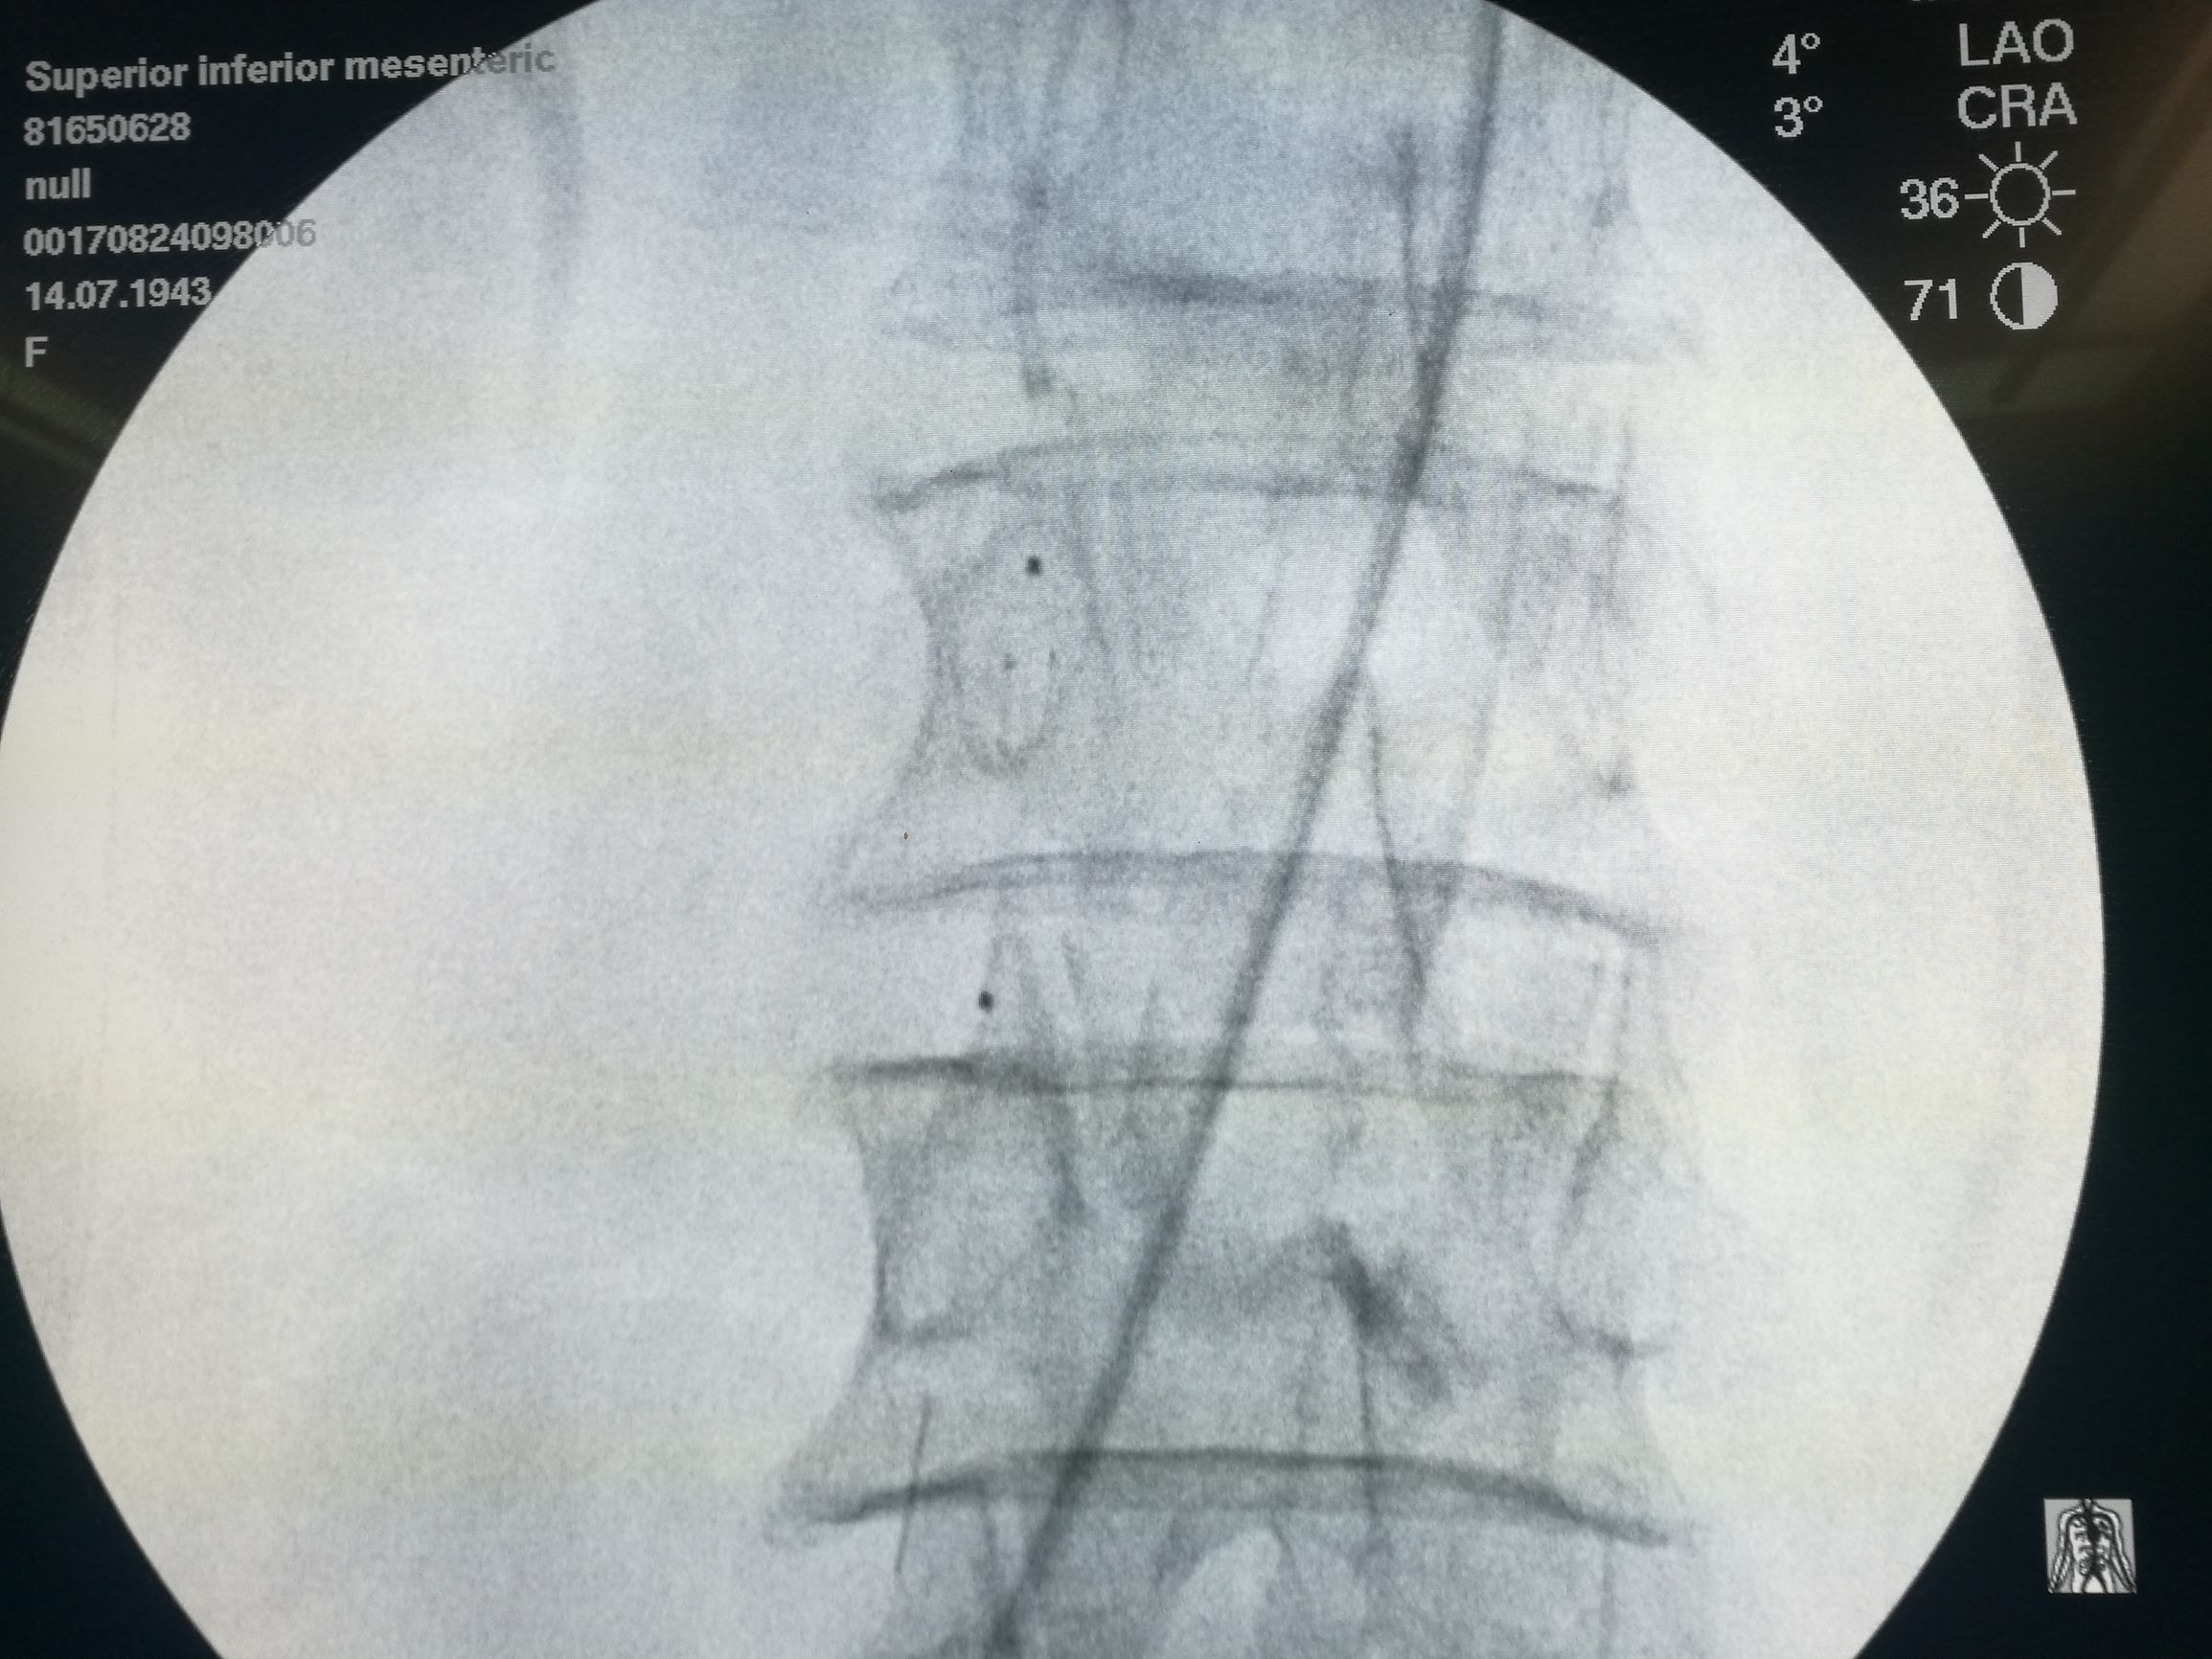

以EV3 SPIDER保护伞取栓(图4)配合6F 指引导管抽吸,取出较多血栓,造影肠系膜上动脉血流通畅

图4. 以Spider保护伞取栓